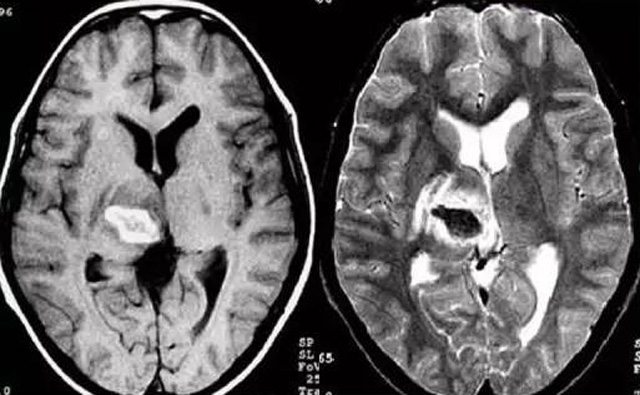

發(fā)現(xiàn)病人出血腦梗相關(guān)癥狀時(shí)候第一時(shí)間就醫(yī),需要攜帶以往的影像檢查資料。向醫(yī)生提供相關(guān)的病史基本資料。做影像檢查時(shí)候需要全身不攜帶金屬物品。檢查時(shí)候身體保持不動,不然偽影對檢查結(jié)果有干擾。磁共振MRI發(fā)現(xiàn)缺血性卒中后,幫助進(jìn)一步查找病因。由于CT上小腦跟腦干顱骨影響,容易導(dǎo)致漏診。MRI檢查可以對CT檢查不足的補(bǔ)充。短暫的腦缺血TIA也需要進(jìn)行影像檢查。短暫性缺血一般10幾分鐘后好轉(zhuǎn)。檢查目的可以確定TIA的病因。降低腦梗死的發(fā)生率。磁共振有助于排出TIA表現(xiàn)的顱內(nèi)病變,有診斷及時(shí)治療的價(jià)值。磁共振MRI檢查時(shí)間比較長,不太適合急診病人。但是可以發(fā)現(xiàn)腦干小腦的出血問題。因?yàn)榧毙阅X梗死的早期和急性期,缺血區(qū)的腦組織還沒有完全壞死,頭顱CT不能顯示病灶,所以就需要MRI磁共振檢查,這個(gè)對陳舊跟亞急性出血顯示比較好。缺點(diǎn)性價(jià)比不高,費(fèi)用比較貴。頭顱的磁共振MRI在發(fā)病后的幾天CT的敏感降低時(shí)候發(fā)揮大作用。,MRI可作為診斷蛛網(wǎng)膜下腔出血和了解破裂動脈瘤部位的一種重要方法,必要時(shí)進(jìn)一步進(jìn)行DSA檢查,幫助制訂臨床的手術(shù)治療方案,